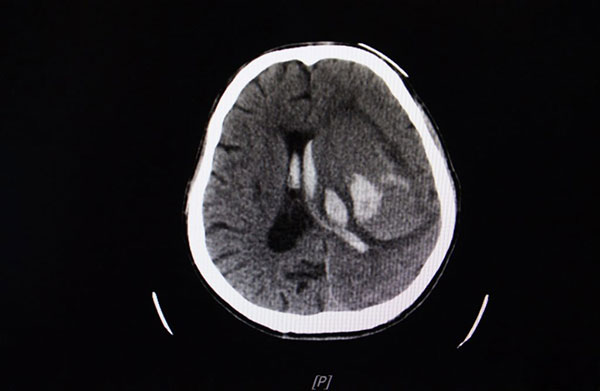

برترینها: آنوریسم مغزی یک برآمدگی یا بادکنک مانند در یکی از شریانهای مغز است که اغلب شبیه میوهای به نظر میرسد که از شاخه آویزان شده. یک آنوریسم مغزی میتواند نشت کرده یا پاره شده و سبب خونریزی در مغز شود (سکته مغزی هموراژیک). بیشتر اوقات یک آنوریسم مغزی در فضای بین مغز و بافت نرم پوشانندهی مغز روی میدهد. این نوع سکته مغزی هموراژیک، خونریزی زیر عنکبوتیه یا ساب آراکنوئید نامیده میشود. پارگی یک آنوریسم خیلی سریع فرد را در وضعیت بسیار خطرناک قرار میدهد و نیاز به اقدام فوری پزشکی دارد.

وقتی یک آنوریسم مغزی پاره میشود، خونریزی آن معمولا تنها چند ثانیه طول میکشد. این خون میتواند آسیب مستقیم به سلولهای پیرامون وارد کند و خونریزی میتواند سلولهای دیگر را از بین ببرد. ضمنا فشار داخل جمجمه نیز افزایش مییابد. اگر این فشار خیلی بالا برود، اکسیژن رسانی و خون رسانی به مغز میتواند تا حدی دچار اختلال شود که هوشیاری از دست برود و یا حتی فرد بمیرد.

- هیدروسفالوس: وقتی پارگی یک آنوریسم موجب خونریزی در فضای بین مغز و بافت اطرافش میشود (که اغلب هم همین اتفاق میافتد)، خون میتواند گردش مایعات اطراف مغز و نخاع را مسدود کند. این عارضه میتواند سبب تجمع مایعات مغزی نخاعی شده و فشار وارد بر مغز بالا برود و به بافتها آسیب برسد.